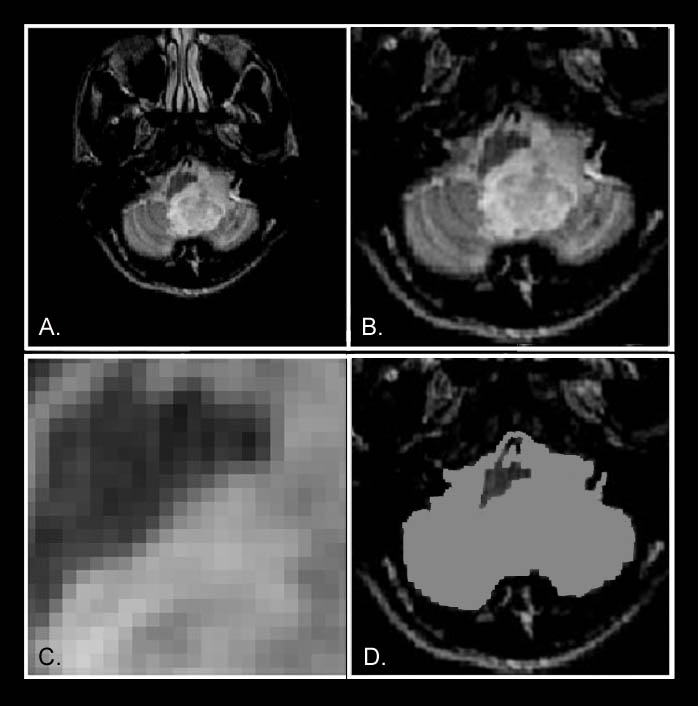

These signal amplitude differences enabled cancer tissues (Figures 11-13) and other tissues to be visualized in MRI images because the signal differences generate the needed brightness differences "PIXEL CONTRAST (IMAGE DETAIL)" in the picture elements (pixels) needed to visualize detail in the MRI image. The CONTRAST

INVISIBLE !! The cerebellar tumor as it would appear (14-D) with no MR signal differences. Figure 14-D is the same image as Figure 14-B but where all MR signal differences were eliminated and all the MR pixels therefore had the same pixel brightness. The absence of the MR signal differences between cancer and normal tissue DISCOVERED BY DAMADIAN gives the MR image pixels equal brightness and NO SIGNAL DIFFERENCES:

PIXEL

(difference in pixel brightness of adjacent image pixels) A typical

medical image is constructed from PICTURE

ELEMENTS designated PIXELS

(Fig 14C) in medical imaging nomenclature.

Fig. 14 A typical

256 X 256 medical image therefore is a composite of

65,536 picture elements

(pixels-Fig 14c) Accordingly the power to visualize DETAIL in the body's CRITICAL SOFT TISSUE VITAL ORGANS (e.g. Brain, Heart, Muscles, Kidney, Liver, Spleen, Pancreas, Intestines) therefore RESTS ENTIRELY on the power of the imaging technology to generate the PIXEL CONTRAST needed to visualize IMAGE DETAIL in the body's vital tissues. The existing x-ray technology for visualizing IMAGE DETAIL in the body's CRITICAL VITAL ORGANS had been severely lacking in its power to generate the PIXEL CONTRAST needed to visualize IMAGE DETAIL in the body's CRITICAL VITAL SOFT-TISSUE ORGANS Dr. Damadian's

Picture Elements (PIXELS):

A typical MRI image is composed of 65,536 PICTURE

ELEMENTS (PIXELS), i.e. a rectangular 256 X

256 PIXEL MATRIX (Fig

10) consists of 256 pixel rows and 256 pixel columns.

The power to visualize detail in any pixel image resides

in the power of the individual image pixel to generate

differences in pixel brightness (PIXEL

CONTRAST)

(Fig 14a, b, c, d)

The differences in the tissue

NMR relaxation times (T1 and T2) of the body's

healthy tissues (131%),

DISCOVERED

by Dr. Damadian (Tables 1 & 2, Fig 6), provided

the signal amplitude differences that generate the

pronounced brightness DIFFERENCES

of the MRI image pixels and produce a 131%

PIXEL CONTRAST for the visualization of ANATOMIC

DETAIL in MRI medical images that had been

limited to a maximum PIXEL

CONTRAST of 4% for visualizing anatomic

detail by x-ray.

Figure 14 is an axial (cross-sectional) image of the brain showing a tumor of the cerebellum (white areas) in the midline. Figure 14c is a magnified image showing the picture elements or "pixels" (small squares) that make up the image. The cerebellar tumor as it would appear (D) with no MR signal differences. Figure D is the same image as B but where all MR signal differences were eliminated and all the MR pixels therefore had the same pixel brightness. The absence of the MR signal differences between cancer and normal tissue discovered by Damadian gives the MR image pixels equal brightness and the tumor becomes Invisible. |

Were the amplitudes of the NMR signals (fig.9) used to set the brightness of each MRI image pixel the same for all tissues (and prior to Dr. Damadian's discovery such NMR tissue signal differences were not known to exist) the brightness of each image pixel would be the same. The MR image would be a blank.

The NMR signal differences discovered by Damadian (Figs 6,9,tables 1 & 2) vary the brightness of the pixels that make up the image (Figs. 6,9). The signal differences of diseased and normal tissues generate the large differences in pixel brightness that enable all diseased tissues (cancerous as well as non-cancerous) to be exquisitely visualized (fig.3b,10,11-13) by the MRI image. Additionally the exceptional NMR signal differences among the normal tissues discovered by Damadian give rise to the extraordinary detail of normal anatomy visualized by MRI (figs. 7,8)